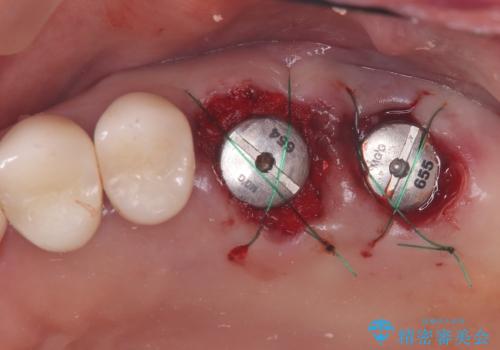

- 左上6番と7番の奥歯に、それぞれ遠心分岐部病変と頬側分岐部に10mmの深い歯周ポケットを認め、慢性的な炎症があります。再根管治療後も経過観察を続けましたが、病状の改善や歯周組織の付着が見られず、外科的歯内療法も選択肢にはありましたが、予後が不確実であること、そして患者様の負担を最小限に抑えたいというご意向を受け、抜歯即時埋入インプラントによる治療計画を立案しました。通常1年ほどかかる治療期間を大幅に短縮し、3ヶ月での機能回復を目指します。

今回のケースでは、特に難しいとされる奥歯の抜歯即時インプラントを適用しました。まず、炎症を起こしていた左上6番と7番を慎重に抜歯し、その直後にインプラントを埋入。この抜歯即時埋入により、歯を失ってからインプラントを埋入するまでの期間を省くことができ、骨の吸収を最小限に抑えられました。痛みや腫れもほとんどなく、患者様は「思ったより楽だった」と仰っていました。結果的に、通常であれば1年近く要する治療をわずか3ヶ月で完了。機能性と審美性を兼ね備えた新しい奥歯により、快適な食生活と笑顔を取り戻していただけました。